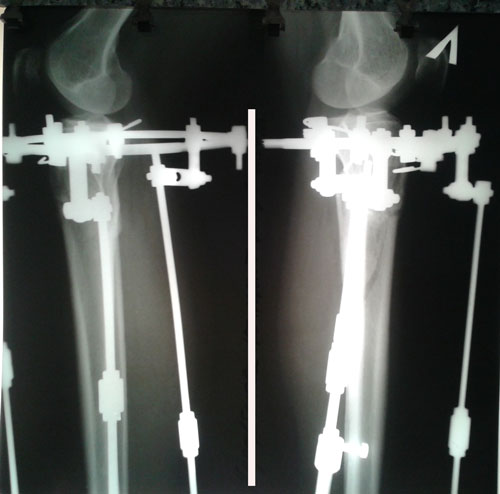

Рентген в 90 дней.

Вложения

20160901_143409.jpg

20160901_143355.jpg